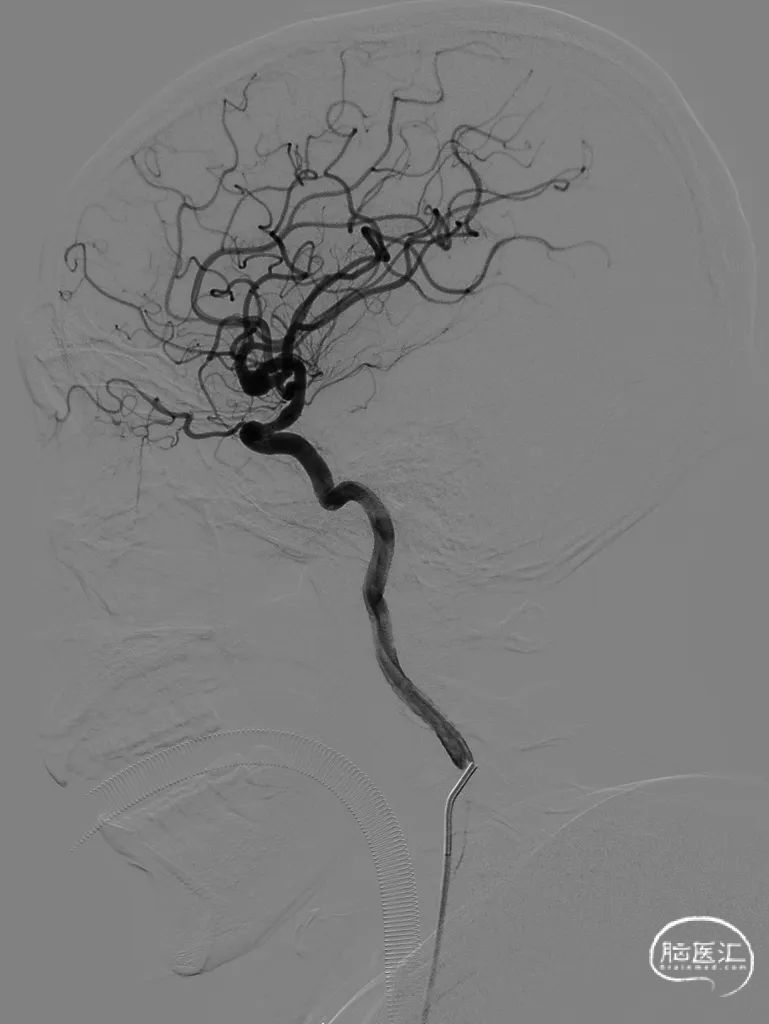

术前DSA的正位、侧位造影。

工作位术前造影及路图。